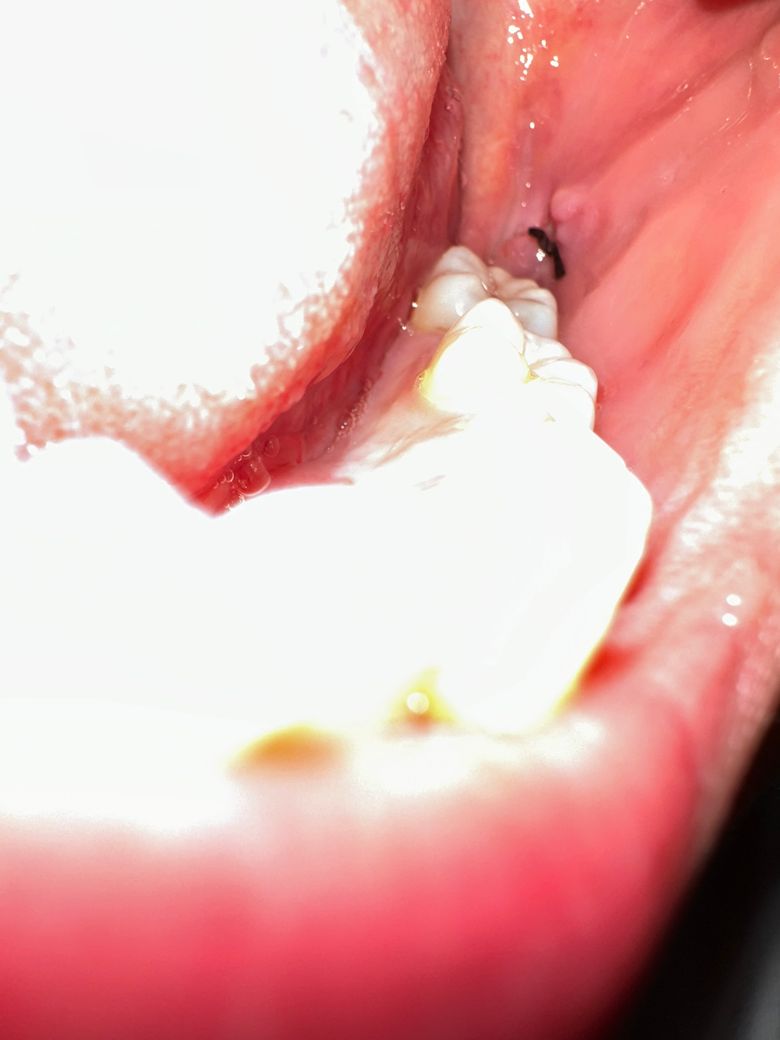

사랑니를 발치한지 50시간이 넘어가고있습니다. 현재 붓기나 통증의 경우 점차 나아지고 있는 상태입니다. 위 사진은 방금 촬영한 사진입니다.

하악 왼쪽 수평매복사랑니 발치인데, 옆볼쪽을 절개해 꿰멘 것 같습니다. 현재 혈병이 탈락한 것인지, 보이지 않는데 불안해 여쭤봅니다. 내부에 흰색의 정체도 궁금합니다!

• 1번 째 사진

2. 혈병은 지금 시기에는 이미 흡수되고 치유를 위한 염증, 육아조직으로 바뀌었을 것입니다.

3. 흰색 물질 보이는게 치유 과정의 염증, 육아조직입니다.

사진으로 봤을 경우에는 혈병이 탈락된것으로 보이지는 않습니다. 너무 걱정하지 않아도 될것으로 생각되며 해당부위가 자극되지 않도록 해주는것이 좋습니다.

겉 혈병은 어느정도 탈락했을 수는 있지만 내부에는 새로운 조직들이 자라나고 있을 것이기 때문에 크게 걱정하지는 않으셔도 됩니다.

흰색은 새로 자라나는 연조직으로 보이고 혹여 음식물이라 하더라도 크게 문제되지 않습니다.